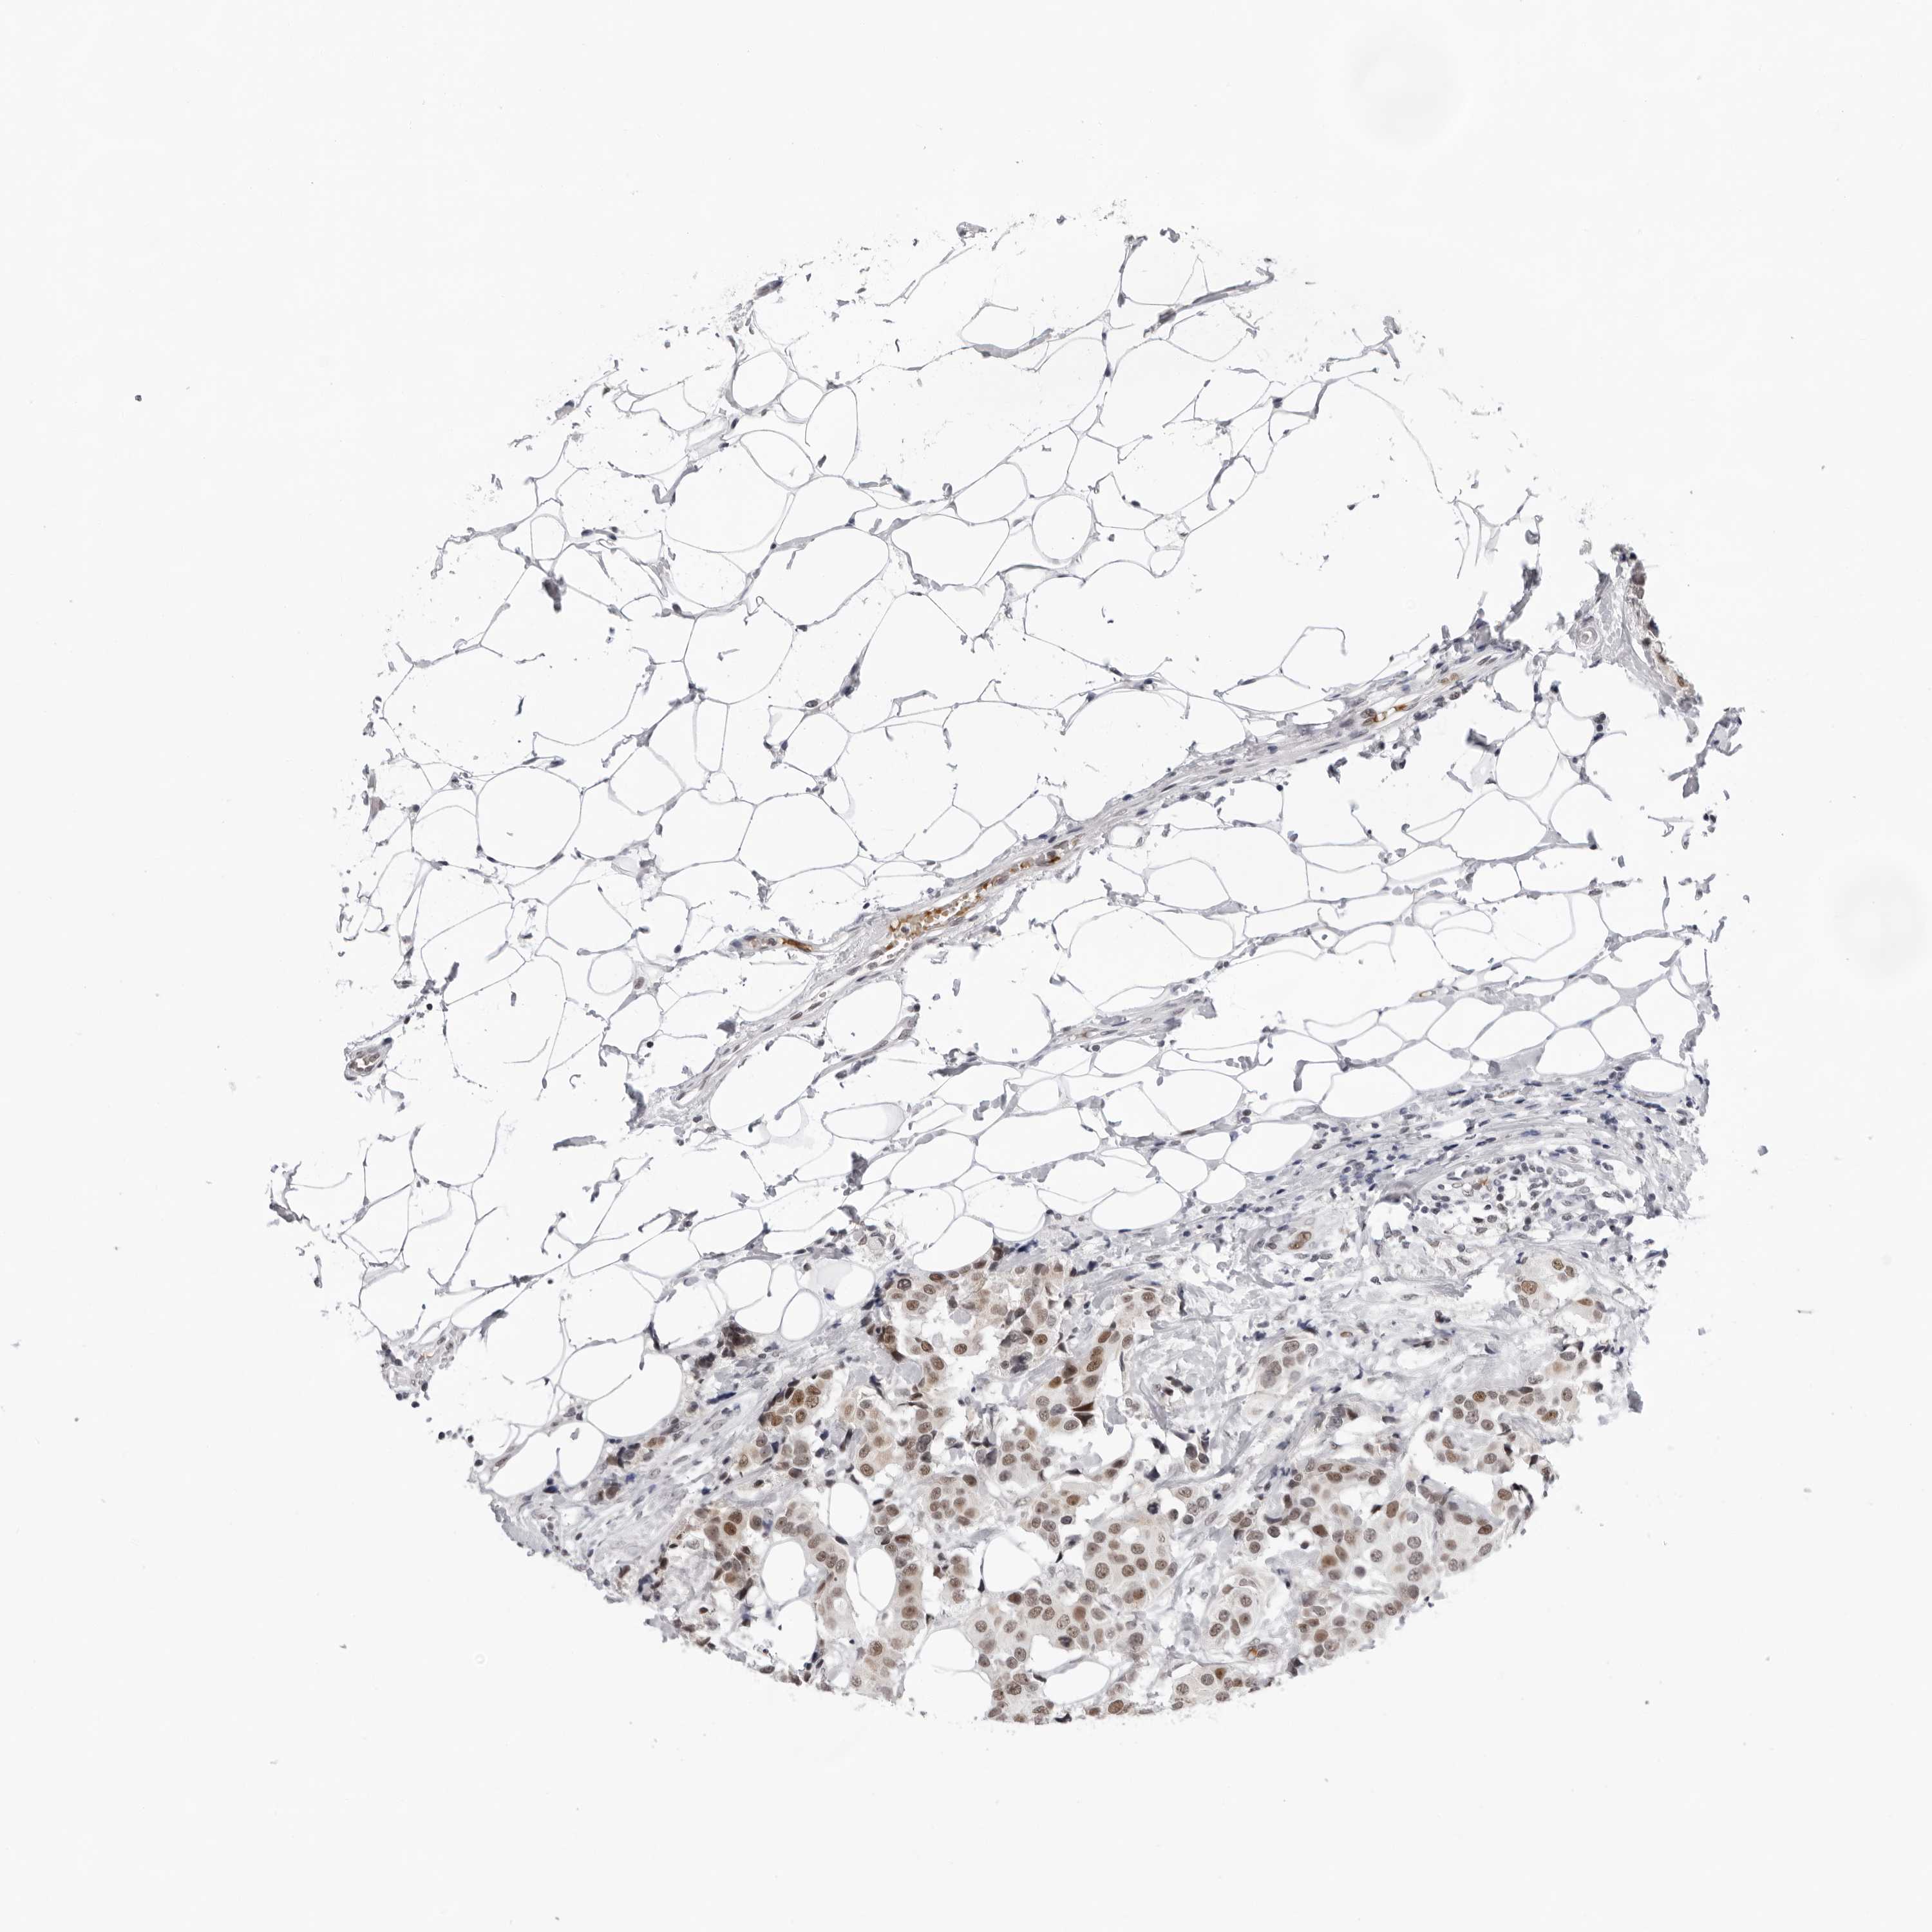

BRCA TCGA BRCA VALIDATION PROTEIN EXPRESSION